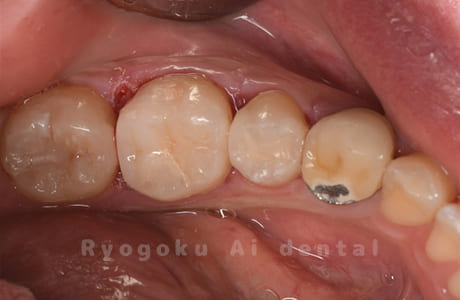

Case06

-

- 原因

- しみる症状がある

- 治療内容

- ジルコニアクラウン

- 治療費用

- 165,000円

他院で治療終了となり、しみる症状があると相談された患者さんです。プラスチックの被せ物の隙間が空いてることとプラスチックの被せ物が大きいため、耐久性と審美性を患者さんと相談し、ジルコニアクラウンで治療を行いました。

<リスク・副作用>

過度の咬合や衝撃で割れることがあります。